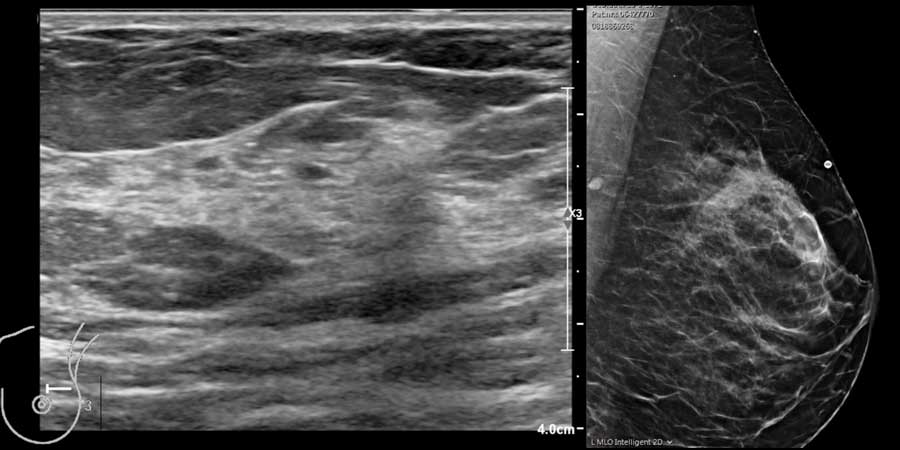

Trong cùng một tuyến vú có thể tồn tại các vùng có nhiều mô mỡ xen kẽ với các vùng chủ yếu là mô xơ tuyến, như có thể thấy trên video.

Hình ảnh vú trên siêu âm có thể khác nhau tùy theo máy của các nhà sản xuất khác nhau.

Điều này có nghĩa là cần làm quen với hình ảnh trên máy siêu âm của chính mình.

Các hình ảnh được chụp từ máy siêu âm Philips (trái) và Siemens (phải).

Hãy chú ý sự khác biệt trong cách hiển thị lớp da chẳng hạn.

Mô xơ tuyến đôi khi phát triển rất dày đặc đến mức chùm tia siêu âm khó có thể xuyên qua được.

Điều này có thể tạo ra hình ảnh giả của một khối giảm âm bờ không đều kèm bóng cản phía sau, dễ nhầm lẫn với ung thư biểu mô (xem video).

Tuy nhiên, khi thực hiện động tác ép nhẹ lên vùng mô này, có thể thấy đây chỉ là mô xơ tuyến tăng âm phát triển rõ rệt.

Thông thường, đây là những bệnh nhân trẻ tuổi đến khám vì khối lớn, đau ở vú.